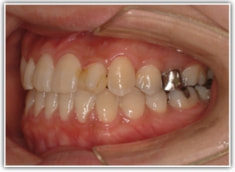

反対咬合ケース

治療法:表の矯正(T21ブラケット)

治療後(1年6ヶ月後)